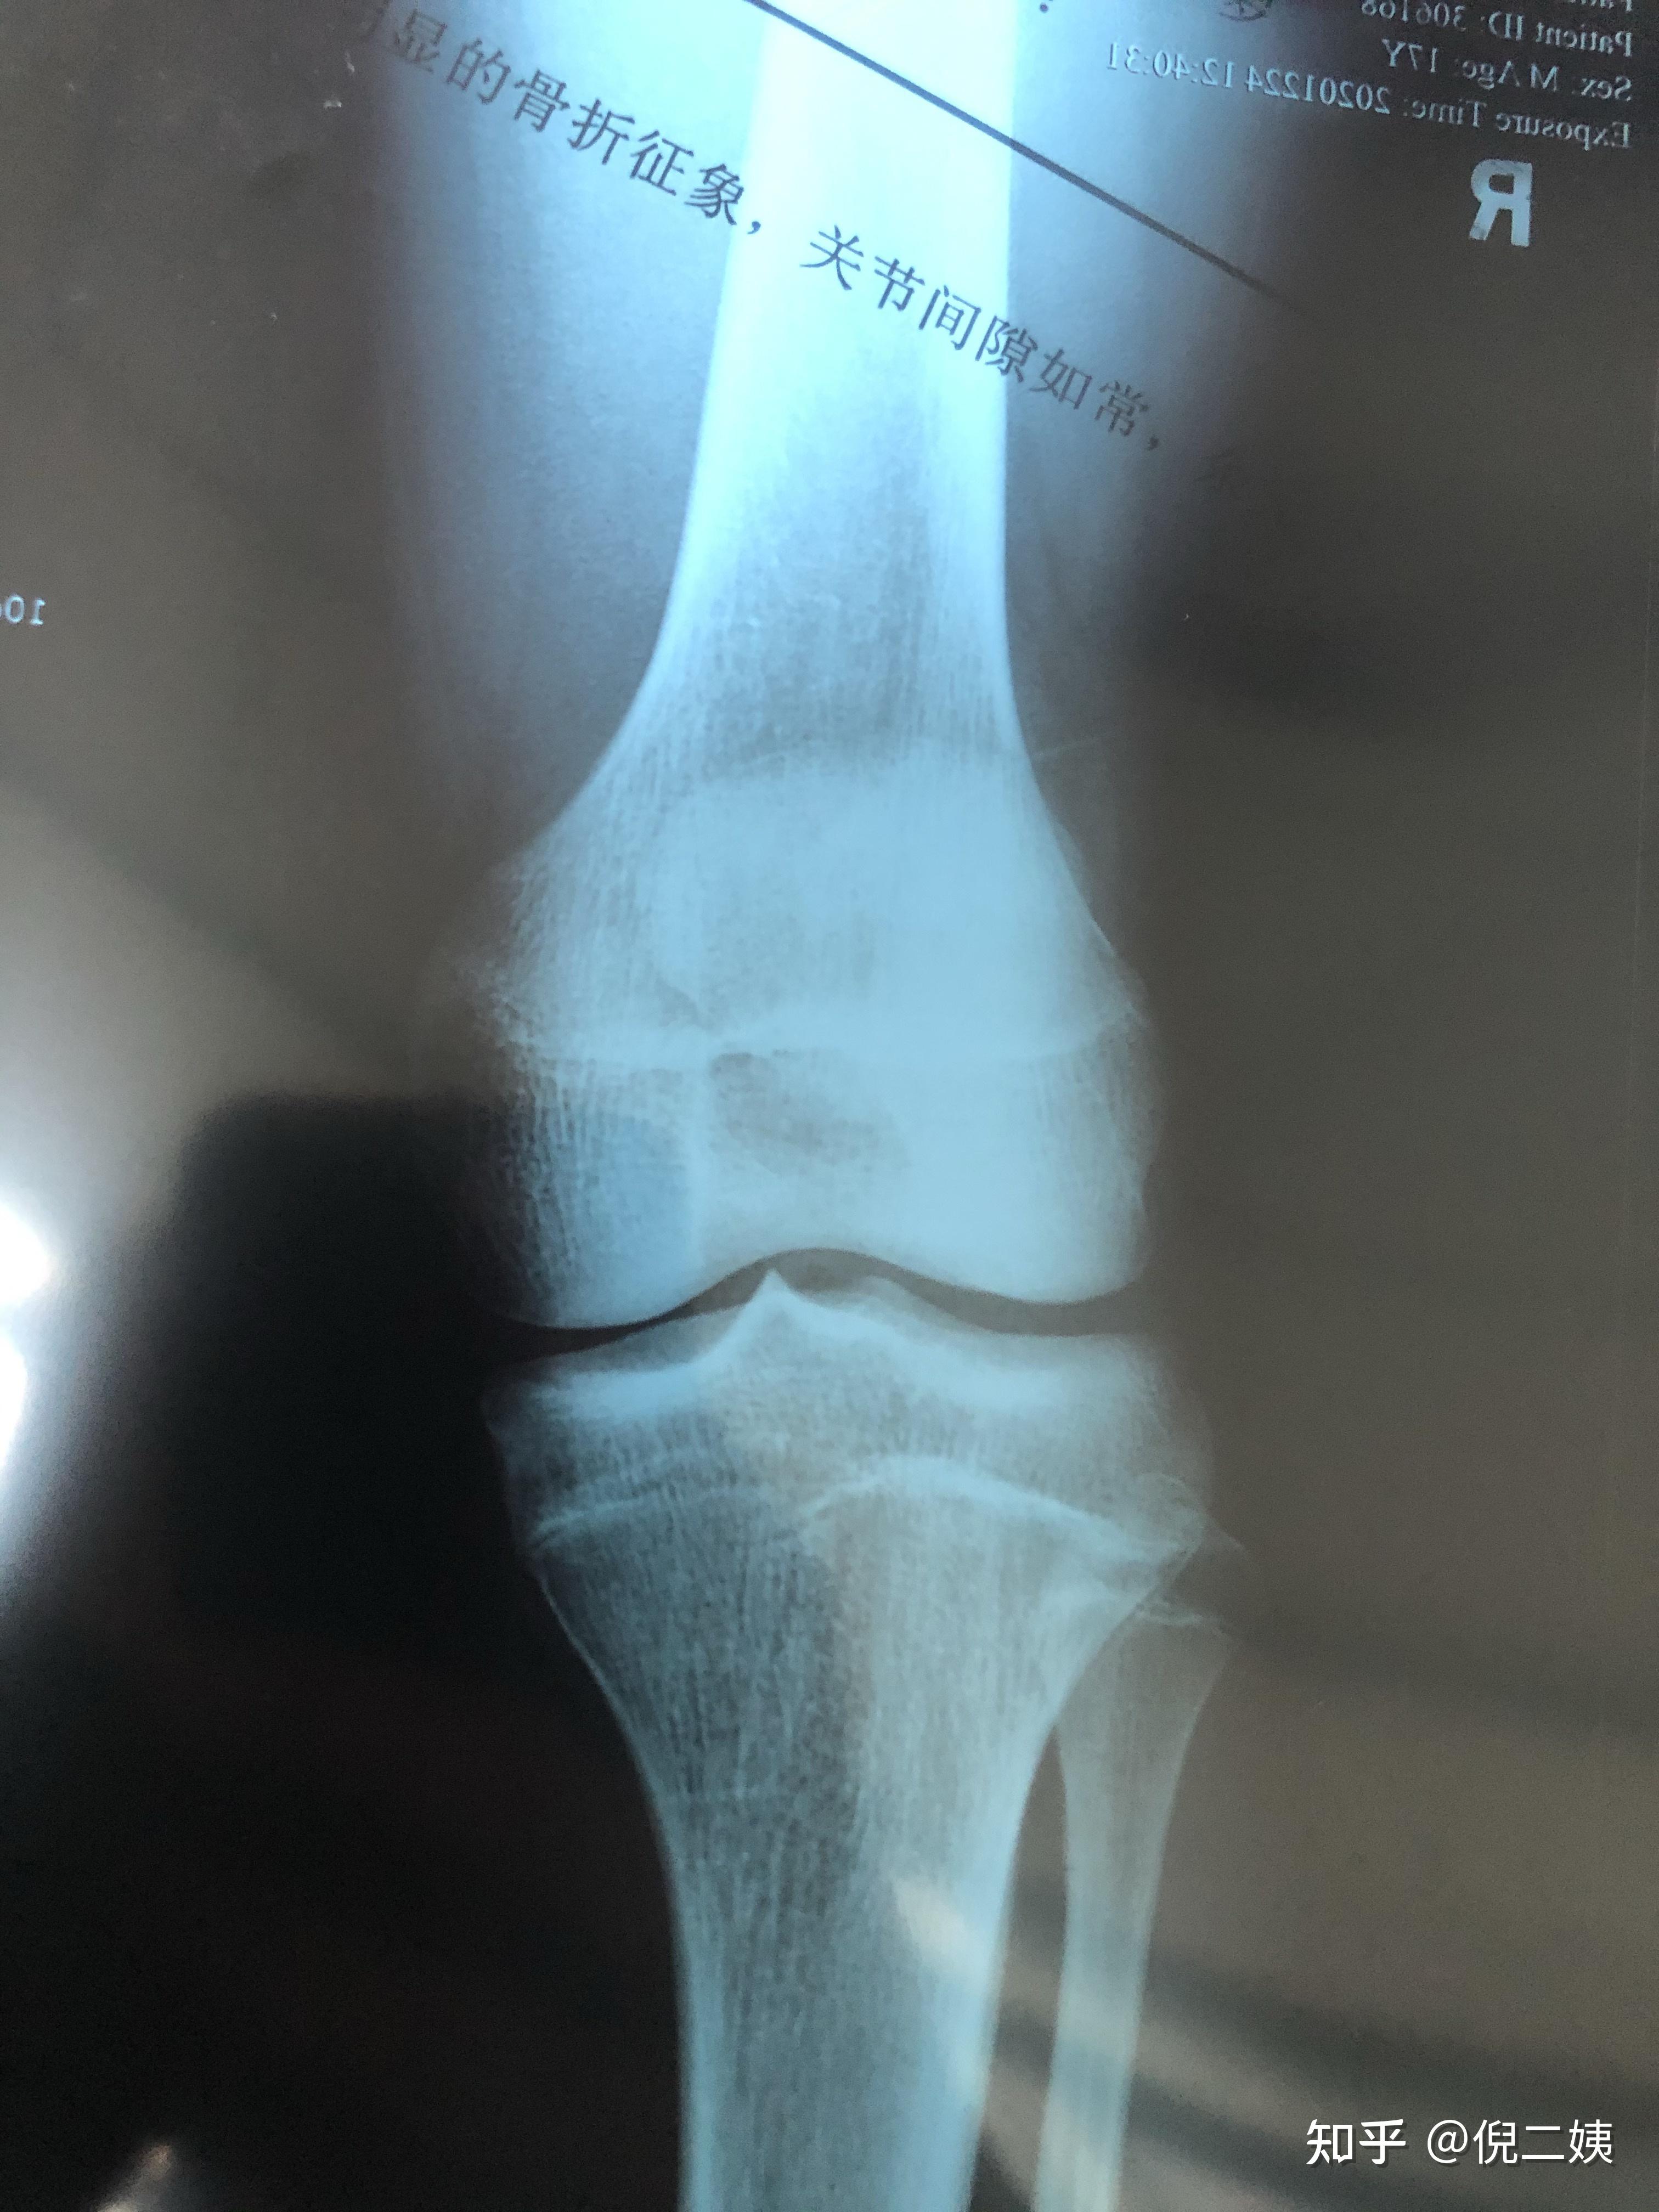

请大家帮忙看下骨骺线是否已闭合,14岁半,男,还能长高吗,上了初中没

图片尺寸1152x864